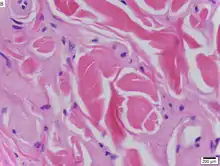

| Urbach–Wiethe disease in skin biopsy with H&E stain. | |

Because Urbach–Wiethe disease is an autosomal recessive condition individuals can be carriers of the disease but show no symptoms. The disease is caused by loss-of-function mutations to chromosome 1 at 1q21, the extracellular matrix protein 1 (ECM1) gene.[12] The dermatological symptoms are caused by a buildup of a hyaline material in the dermis and the thickening of the basement membranes in the skin.[9] Urbach–Wiethe disease is typically diagnosed by its clinical dermatological manifestations, particularly the beaded papules on the eyelids. The discovery of the mutations within the ECM1 gene has allowed the use of genetic testing to confirm an initial clinical diagnosis. Periodic acid-Schiff (PAS) and immunohistochemical staining may also be used for diagnosis.[6][13]

The dermatological symptoms are caused by a buildup of a hyaline material in the dermis and the thickening of the basement membranes in the skin.[9] The nature of this material is unknown, but researchers have suggested that it may be a glycoprotein, a glycolipid, an acid mucopolysaccharide, altered collagen or elastic tissue.[6]

Urbach–Wiethe disease is typically diagnosed by its clinical dermatological manifestations, particularly the beaded papules on the eyelids. Doctors can also test the hyaline material with a periodic acid-Schiff (PAS) staining, as the material colors strongly for this stain.[6]

Immunohistochemical skin labeling for antibodies for the ECM1 protein as labeling has been shown to be reduced in the skin of those affected by Urbach–Wiethe disease.[13] Staining with anti-type IV collagen antibodies or anti-type VII collagen antibodies reveals bright, thick bands at the dermoepidermal junction.[9]